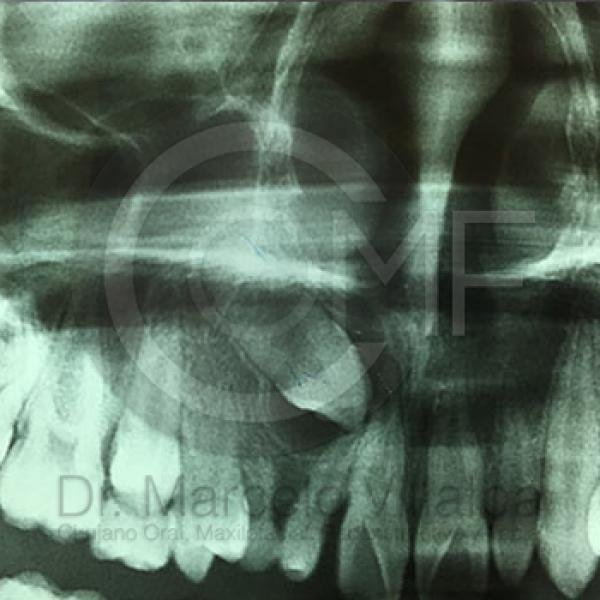

Contenido Sensible y Gráfico

Si usted no pertenece al área de la salud, las imágenes pueden ser muy explícitas.